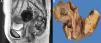

A 58-year-old woman had a past medical history of clinical stage IIB (FIGO) cervical cancer (squamous cell carcinoma), treated with chemotherapy (CT) based on 4 cycles of cisplatin and concomitant radiotherapy (RT) of 50Gy to the pelvis and brachytherapy (BT) of 35Gy. She had complete response and was kept under surveillance. Eight years later, with no apparent recurrence, the patient presented with rectal tenesmus associated with rectal bleeding. Physical examination revealed an ulcerated exophytic tumor 3cm from the anal margin that occluded 50% of the lumen, with no apparent involvement of the rectovaginal septum. Rectosigmoidoscopy identified the tumor at 6cm from the anal margin, occluding up to 70% of the lumen. Biopsy revealed mesenchymal neoplasia with the following immunoprofile: positive actin, negative CD34, CD117, DOG1, PS100, CKAE1/AE3, and P16. The diagnosis was high-grade leiomyosarcoma. Nuclear magnetic resonance (NMR) imaging corroborated the dependence on the rectal wall, as well as the involvement of the muscles of the perineum and the fat of both buttocks in the anal region (fig. 1). The rest of the extension studies were negative for distant disease. The multidisciplinary team began treating the patient with induction CT (doxorubicin and gemcitabine), after performing a sigmoid loop diversion colostomy. Response to the third CT cycle was partial and total pelvic exenteration with vulvectomy was indicated. Intraoperative findings were a tumor in the perineal region involving the gluteus maximus and levator ani muscles, with no separating plane of the uterus and bladder. Urinary reconstruction through ileal conduit and diversion colostomy was performed. The patient had adequate progression with no complications. Surgical specimen examination corroborated the differentiation to high-grade smooth muscle tumor. It measured 7 x 4 x 3cm, compromising the perineal edge up to the rectovaginal septum and infiltrating the anal sphincter muscles and skin. There was also lymphovascular and perineural invasion. The surgical margins were free from neoplasia and the immunohistochemistry pattern was similar to the previous one, adding positive P53 and Ki67 in 1% and 90% of the neoplastic cells, respectively (fig. 2).